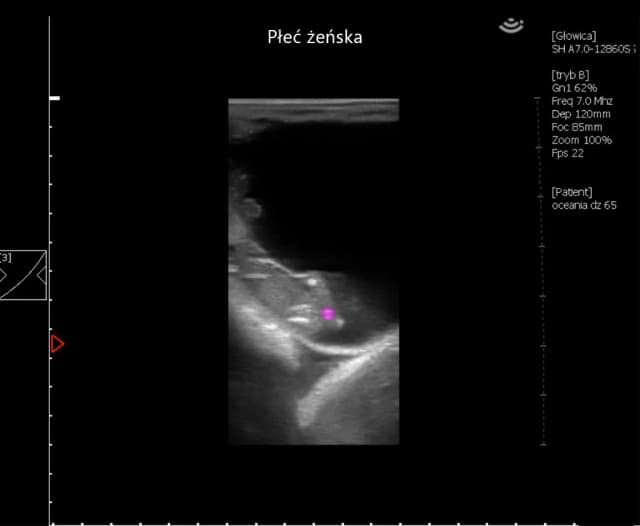

Tag kiedy można rozpoznać ciążę u konia